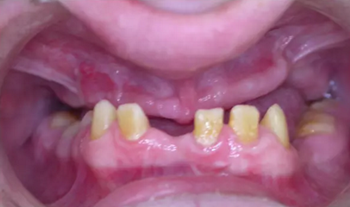

圖 4. 術(shù)前口內(nèi)照

該患者 12 歲時(shí)已診斷為釉質(zhì)發(fā)育不全。家族史正常,否認(rèn)全身系統(tǒng)性疾病。全身系統(tǒng)檢查無(wú)明顯異常,檢查雙側(cè)顳下頜關(guān)節(jié)、開(kāi)口度正常??趦?nèi)及 X 片檢查見(jiàn)上頜縮窄,上頜牙列缺失,安氏三類錯(cuò)牙合,下頜牙牙冠短小,牙根正常。上頜大量牙槽骨因以前手術(shù)干預(yù)而喪失,后牙區(qū)牙槽骨高于前牙區(qū)。病變牙齒在之前的治療中已被拔除。